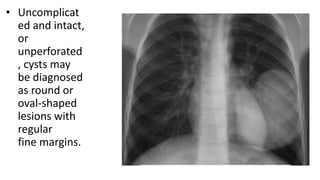

• Uncomplicat

ed and intact,

or

unperforated

, cysts may

be diagnosed

as round or

oval-shaped

lesions with

regular

fine margins.